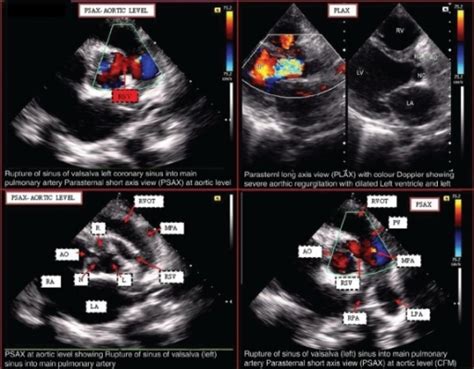

Surgical Approach to Left Ventricular Inflow Obstruction ...

Surgical Approach to Left Ventricular Inflow Obstruction ... from www.annalsthoracicsurgery.org